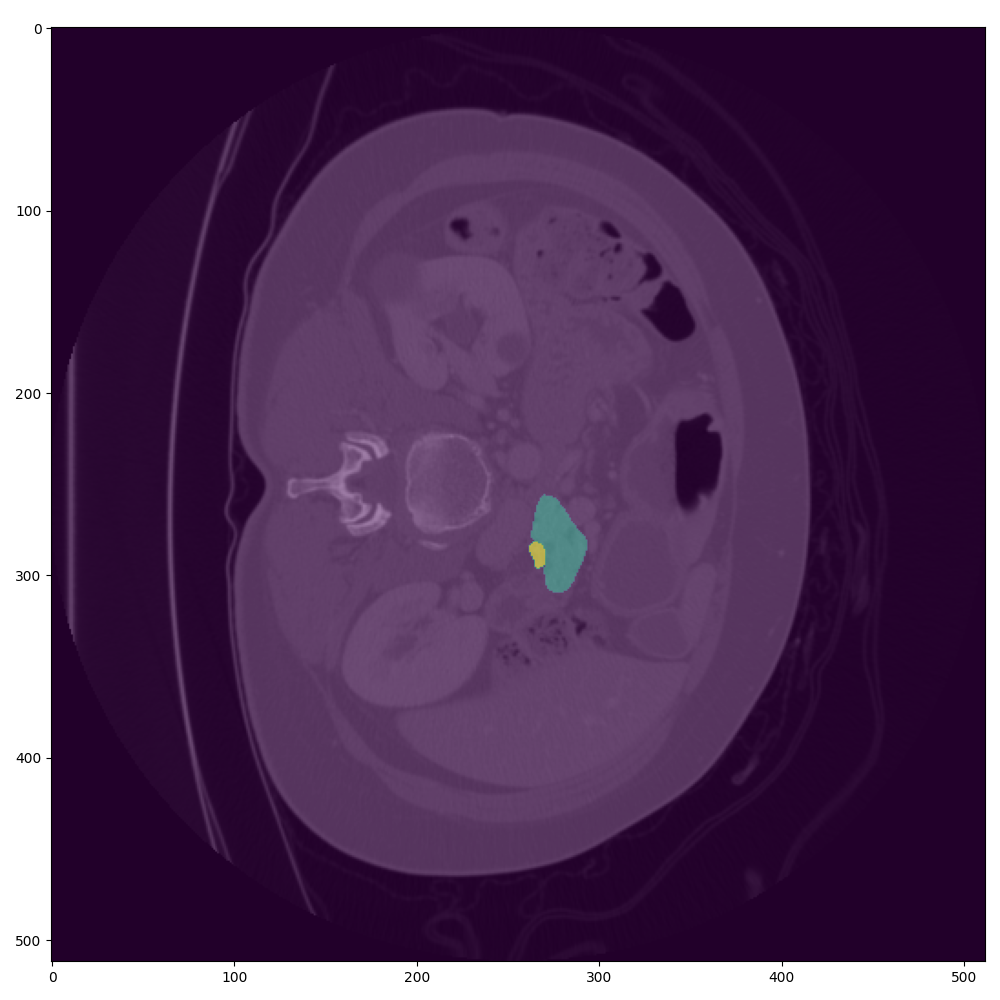

- ๐ผ๏ธ Advanced Imaging Analysis: Enhances diagnostic accuracy through integrated CT scan analysis using Nvidia MONAI [1].

- ๐ง AI Modeling: Optimized LightGBM models combined with Cohereโs RAG for interpretability, coupled with Nvidia MONAI.